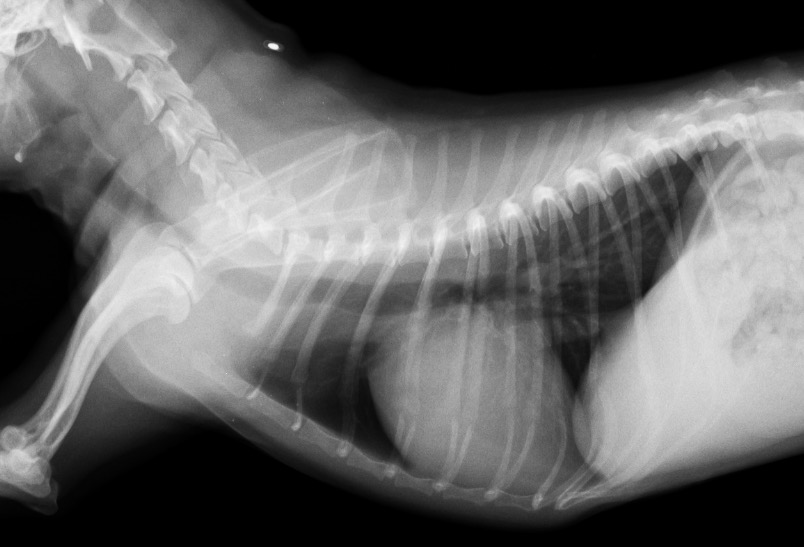

1年後のレントゲン検査 心陰影の縮小